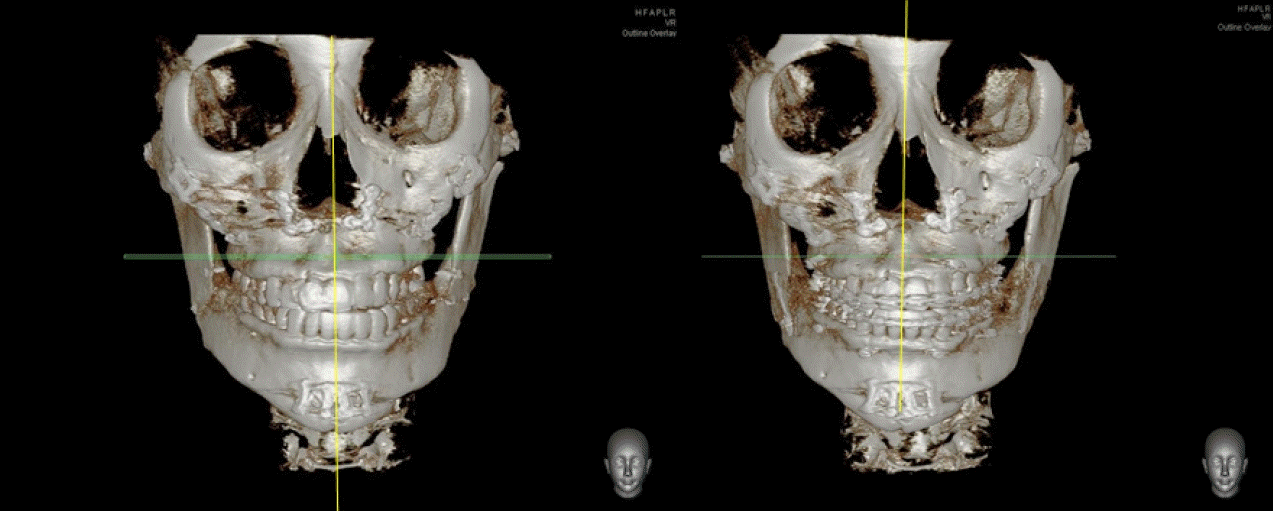

32세 여성이 우측 턱관절의 통증과 개구제한을 주소로 내원하였다. 내원 전에 3차례에 걸쳐 각각 다른 의료기관에서 턱교정수술을 받은 경험이 있고, 음식물 저작이 힘들고 입이 비뚤어져 사회관계에도 문제가 있었다. 안모는 좌측으로 변위된 비대칭이 관찰되었고 교합은 상악골의 우측 변위, 하악골의 경사진 좌측 변위로 인해 치아 중심선 비대칭을 포함하여 전치부의 개방교합과 구치부의 반대교합이 관찰되었다(Fig. 5). 우측 관절부위 통증과 다수의 수술로 인한 저작근 주위 조직의 경직으로 인해 자발적 최대개구량은 23mm이었다. 파노라마방사선영상에서 우측 하악과두가 좌측에 비해 glenoid fossa으로 부터 떨어져 있고 전방으로 기울어져 있는 것을 관찰할 수 있었다(Fig. 6). 이전 하악골편 고정시 하악과두가 포함된 근심골편이 후방으로 위치하여 고정된 것과 상악골의 우측 변위되어 고정된 것을 개선시키기 위해 4번째 턱교정재수술(4th reoperation)과 치아교정술을 계획하였다. 상악골의 수술 시 하악골의 안정을 위해 후상방이동 2.5mm와 기울어진 교합평면의 개선을 위해 교합평면 수정1.5mm를 하였으며 동시에 상악의 비대칭 개선을 위해 좌측으로 1.5mm 측방이동하였다. 하악골은 기존의 골절선을 이용하여 골편을 분리한 후 변위된 우측 근심골편을 관절와에 재위치시키고 상악골의 위치에 따라 고정하였다. 수술 중 비대칭이 해소된 것과 개구량 45mm 확보된 것을 확인하였다. 수술 후 파노라마방사선영상과 3D CT영상에서 치아의 정중선이 일치하고 전치부 및 구치부의 반대교합이 해소된 것을 볼 수 있었다. 그리고 우측 하악과두가 관절강 내 재위치된 것과 하악지의 방향이 좌, 우측 비슷하다는 것을 확인할 수 있었다(Figs. 7 and 8). 수술 후 2주부터 개구연습과 치아 교정을 진행하였으며, 수술 후 3개월에 자발적 개구량 35mm 확인하였다. 다수의 수술로 인한 구강내 반흔 조직과 저작근 주위의 경결감으로 인해 적극적인 개구훈련을 하였으며 수술 후 6개월에 38mm의 개구량을 보였으나 통증은 없고 일상식이 가능하여 이후의 경과관찰에는 내원하지 않았다.- 증례 3